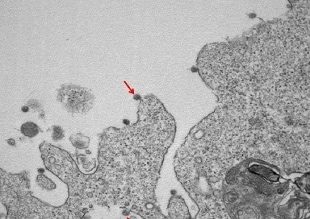

Si vede anche la famosa 'corona', nel primo ritratto in bianco e nero del virus SarsCoV2 isolato in Lombardia all'Ospedale Sacco di Milano: le immagini al microscopio elettronico mostrano le particelle virali attaccate alle membrane delle cellule e la loro tipica corona di glicoproteine superficiali. L'annuncio in una nota dell'Università Statale di Milano.

Il coronavirus era stato isolato presso il Laboratorio di Malattie Infettive dal gruppo coordinato da Massimo Galli e Gianguglielmo Zehender, in collaborazione con l'Anatomia Patologica diretta da Manuela Nebuloni del Dipartimento di Scienze Biomediche e Cliniche Luigi Sacco. A ottenere gli isolamenti sono stati i ricercatori Alessia Lai, Annalisa Bergna, Arianna Gabrieli e Maciej Tarkowski, mentre Antonella Tosoni e Beatrice Marchini hanno effettuato le osservazioni al microscopio elettronico e prodotto le bellissime immagini.

Nella prima, a un ingrandimento di 30000X, si osservano le particelle virali di SarsCov2 (indicate dalle frecce), adese alle membrane sulla superficie e all'interno di cellule utilizzate per l'isolamento. La combinazione di altre due immagini a diverso ingrandimento (50000X e 140000X) mostra invece le particelle virali con la tipica ultrastruttura caratterizzata dalla corona di glicoproteine superficiali.